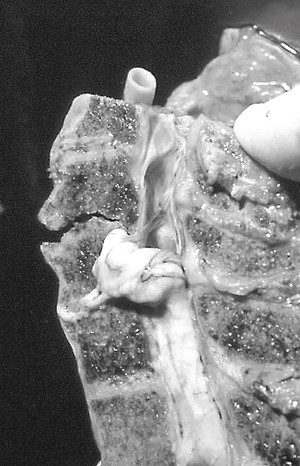

Det er nærmest horisontale leddflater mellom C1 og C2, i motsetning til hos menneskeapene, hvor de skrår ca. 45° nedover i lateral retning slik at C1 blir liggende som en stabil «ring» utenpå C2 (1). I begge tilfeller tillater atlantoaksialleddet rotasjon, og kalles derfor «nei-leddet». Leddkapselen er tynn og vid, og med kraftige synoviale folder som noen ganger kan legge seg inn i leddspalten (5). Vekten av hodet (pluss halsmuskulaturens tonus/kontraksjonskraft) fordeles på atlantooksipitalleddene, overføres til de to atlantoaksialleddene, og derfra til mellomvirvelskiven C2–C3. Axis blir derfor et element i halsvirvelsøylen hvor de laterale kreftene sentraliseres (fig 1).

Mens virvellegemene er bærende, er de skråttstilte fasettleddene styrende for bevegeligheten mellom virvlene. De motstår sagittale krefter bakfra (mens det ved tilsvarende krefter forfra kun er ligamentene som holder igjen), med unntak av dens axis, som stikker opp bak fremre bue på C1. Dens danner et synovialt ledd mot C1 i en grop (fovea dentis) på innsiden av buen. Den bakre flaten artikulerer med et tversgående ligament (ligamentum transversum atlantis) som danner et ekte ledd, idet ligamentet har en hinne av fiberbrusk som artikulasjonsflate. Den sidestøtten som processus uncinatus representerer, gjelder ikke for C1, som kun har en viss sidestøtte i fovea dentis ved hjelp av ligamentene omkring. Det gjør atlantoaksialleddet særlig sårbart ved krefter som virker sideveis og bakfra, mens de øvrige delene av cervikalcolumna i mindre grad tåler krefter som virker forfra.